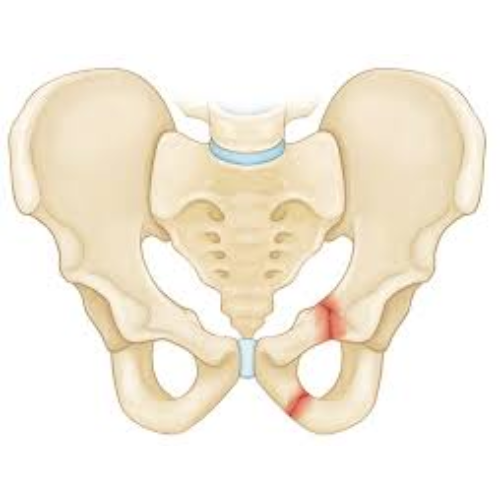

Libia (Iliac) Fractures

A Libia (iliac) fracture is a break in the iliac bone, which forms the upper part of the pelvis. These fractures often occur due to high-impact trauma, such as road accidents, falls from height or severe sports injuries. Treatment may involve rest, pain management, physical therapy or surgery depending on the severity and displacement of the fracture.

Who Needs It?

• Patients with severe pelvic or hip pain after trauma.

• Individuals who have difficulty walking or bearing weight on the affected side.

• Patients with visible deformity or swelling in the pelvic area.

• Those with associated injuries that require surgical intervention to stabilize the pelvis.

Benefits:

• Reduces pain and prevents complications like pelvic instability or chronic discomfort.

• Promotes proper bone healing and restores pelvic alignment.

• Enhances mobility and helps return to daily activities safely.

• Minimizes the risk of long-term issues such as arthritis, gait problems or nerve damage.